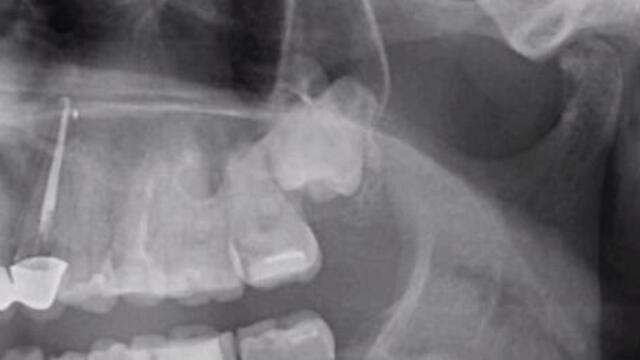

Отстраняване на ретиниран мъдрец - Impacted Tooth Removal - Videoclip.bg

Гледай Отстраняване на ретиниран мъдрец - Impacted Tooth Removal, видео качено от mentos, във Videoclip.bg - видео споделяне за всички българи!